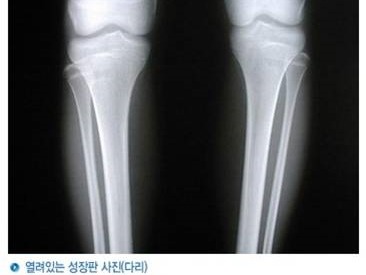

성장판이 열려 있어야 키가 큰다

열려있는 성장판 사진(다리)

성장판이 닫히는 순서는 손가락 ,발가락->무릎->손목->척추 순입니다.

성장검사에서는 성장호르몬검사, 뼈나이, 성장판검사가 가능합니다.